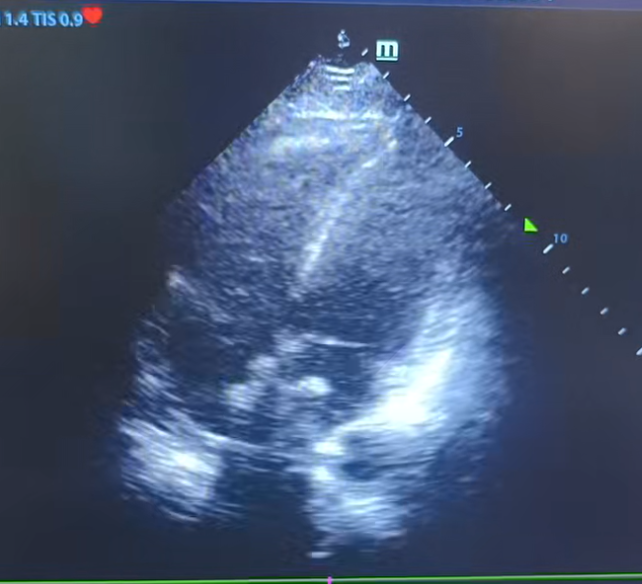

经过全面检查,经食道超声心动图提示,房间隔中部回声中断,房水平左向右分流;右心声学造影结果阳性(固有型,Ⅱ级),右向左分流。确诊先天性心脏病-房间隔缺损,介入封堵指征明显。

手术当日,心血管内科团队提前制订周密介入方案。术中,团队经股静脉穿刺建立通路,将输送鞘管送达心脏房间隔缺损部位,精准释放可降解封堵器,整个操作在X线透视和超声心动图的引导下完成。患者全程无明显痛感,术后次日即下床活动。

术后超声X线透视影像